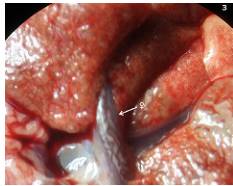

Posteriormente, se examinaron las heces para observar si había larvas L1 de A. cantonensis. Se examinó la cavidad torácica (corazón, arterias pulmonares y pulmones) en busca de los nematodos parásitos, juveniles o adultos. Se contaron los nematodos adultos encontrados en la luz de la arteria pulmonar y se guardaron en una solución de formaldehído al 3 % 11 (figuras 2, 3 y 4).

Los parásitos se encontraron en la aurícula derecha del corazón en la mayoría (55/68) de los casos. En el corazón y en los pulmones se observaron algunas zonas hemorrágicas, fibrosis y abscesos.